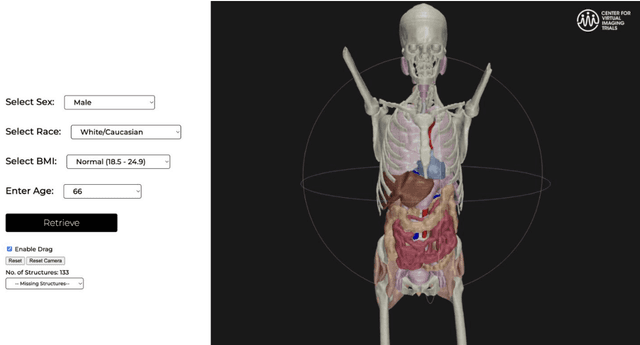

Abstract:Virtual Imaging Trials (VIT) offer a cost-effective and scalable approach for evaluating medical imaging technologies. Computational phantoms, which mimic real patient anatomy and physiology, play a central role in VIT. However, the current libraries of computational phantoms face limitations, particularly in terms of sample size and diversity. Insufficient representation of the population hampers accurate assessment of imaging technologies across different patient groups. Traditionally, phantoms were created by manual segmentation, which is a laborious and time-consuming task, impeding the expansion of phantom libraries. This study presents a framework for realistic computational phantom modeling using a suite of four deep learning segmentation models, followed by three forms of automated organ segmentation quality control. Over 2500 computational phantoms with up to 140 structures illustrating a sophisticated approach to detailed anatomical modeling are released. Phantoms are available in both voxelized and surface mesh formats. The framework is aggregated with an in-house CT scanner simulator to produce realistic CT images. The framework can potentially advance virtual imaging trials, facilitating comprehensive and reliable evaluations of medical imaging technologies. Phantoms may be requested at https://cvit.duke.edu/resources/, code, model weights, and sample CT images are available at https://xcat-2.github.io.